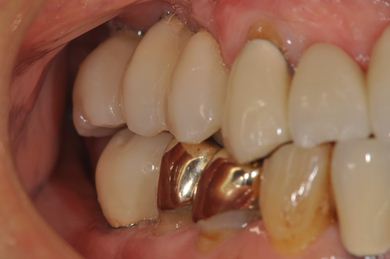

インプラントの症例写真 IMPLANT

| 治療内容 | インプラント8本(抜歯即日スピードインプラント、サイナスリフト)、ハイブリッドセラミック8本 | ||||||||||||||||||||||||||||||||

| 治療期間 | 1年0ヶ月 |